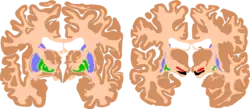

The basal ganglia plays essential roles in voluntary motor function. Various forms of damage to the basal ganglia can cause a range of movement disorders.

Like other forms of CP, it is primarily associated with damage to the basal ganglia in the form of lesions that occur during brain development due to bilirubin encephalopathy and hypoxic–ischemic brain injury.[7]

Hypoxic-ischemic brain injury is a form of cerebral hypoxia in which oxygen cannot perfuse to cells in the brain. Lesions in the putamen and thalamus caused by this type of brain injury are primary causes of ADCP and can occur during the prenatal period and shortly after.[7] Lesions that arise after this period typically occur as a result of injury or infections of the brain.[18]

Bilirubin encephalopathy, also known as kernicterus, is the accumulation of bilirubin in the grey matter of the central nervous system. The main accumulation targets of hyperbilirubinemia are the basal ganglia, ocular movement nucleus, and acoustic nucleus of the brainstem.[7] Pathogenesis of bilirubin encephalopathy involves several factors, including the transport of bilirubin across the blood–brain barrier and into neurons.[7] Mild disruption results in left cognition impairment, while severe disruption results in ADCP.[7] Lesions caused by accumulation of bilirubin occur mainly in the global pallidus and hypothalamus.[7] Disruption of the blood–brain barrier by disease or a hypoxic ischemic injury can also contribute to an accumulation of bilirubin in the brain.[7] Bilirubin encephalopathy leading to cerebral palsy has been greatly reduced by effective monitoring and treatment for hyperbilirubinemia in preterm infants.[7] As kernicterus has decreased due to improvements in care, over the last 50 years the proportion of children developing athetoid CP has decreased.[19] In most cases, will have normal intelligence.

Multiple classification systems using magnetic resonance imaging (MRI) have been developed, linking brain lesions to time of birth, cerebral palsy subtype and functional ability.[23][24][25][26] Around 70% of patients with DCP show lesions in the cortical and deep grey matter of the brain, more specifically in the basal ganglia and thalamus. However, other brain lesions and even normal-appearing MRI findings can occur, for example white matter lesions and brain maldevelopments.[2][25][27][28] Patients with pure basal ganglia and thalamus lesions are more likely to show more severe choreoathetosis whereas dystonia may be associated with other brain lesions, such as the cerebellum.[2] These lesions occur mostly during the peri- and postnatal period since these regions have a high vulnerability during the late third trimester of the pregnancy.[29] Unfortunately, contemporary imaging is not sophisticated enough to detect all subtle brain deformities and network disorders in dystonia. Research with more refined imaging techniques including diffusion tensor imaging and functional MRI is required.[10][30]